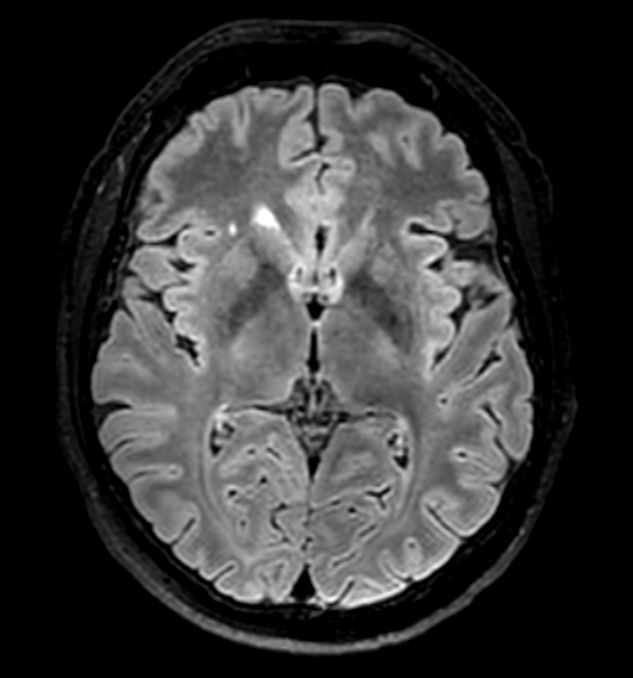

Axial DWI b1000 (ADC)

-